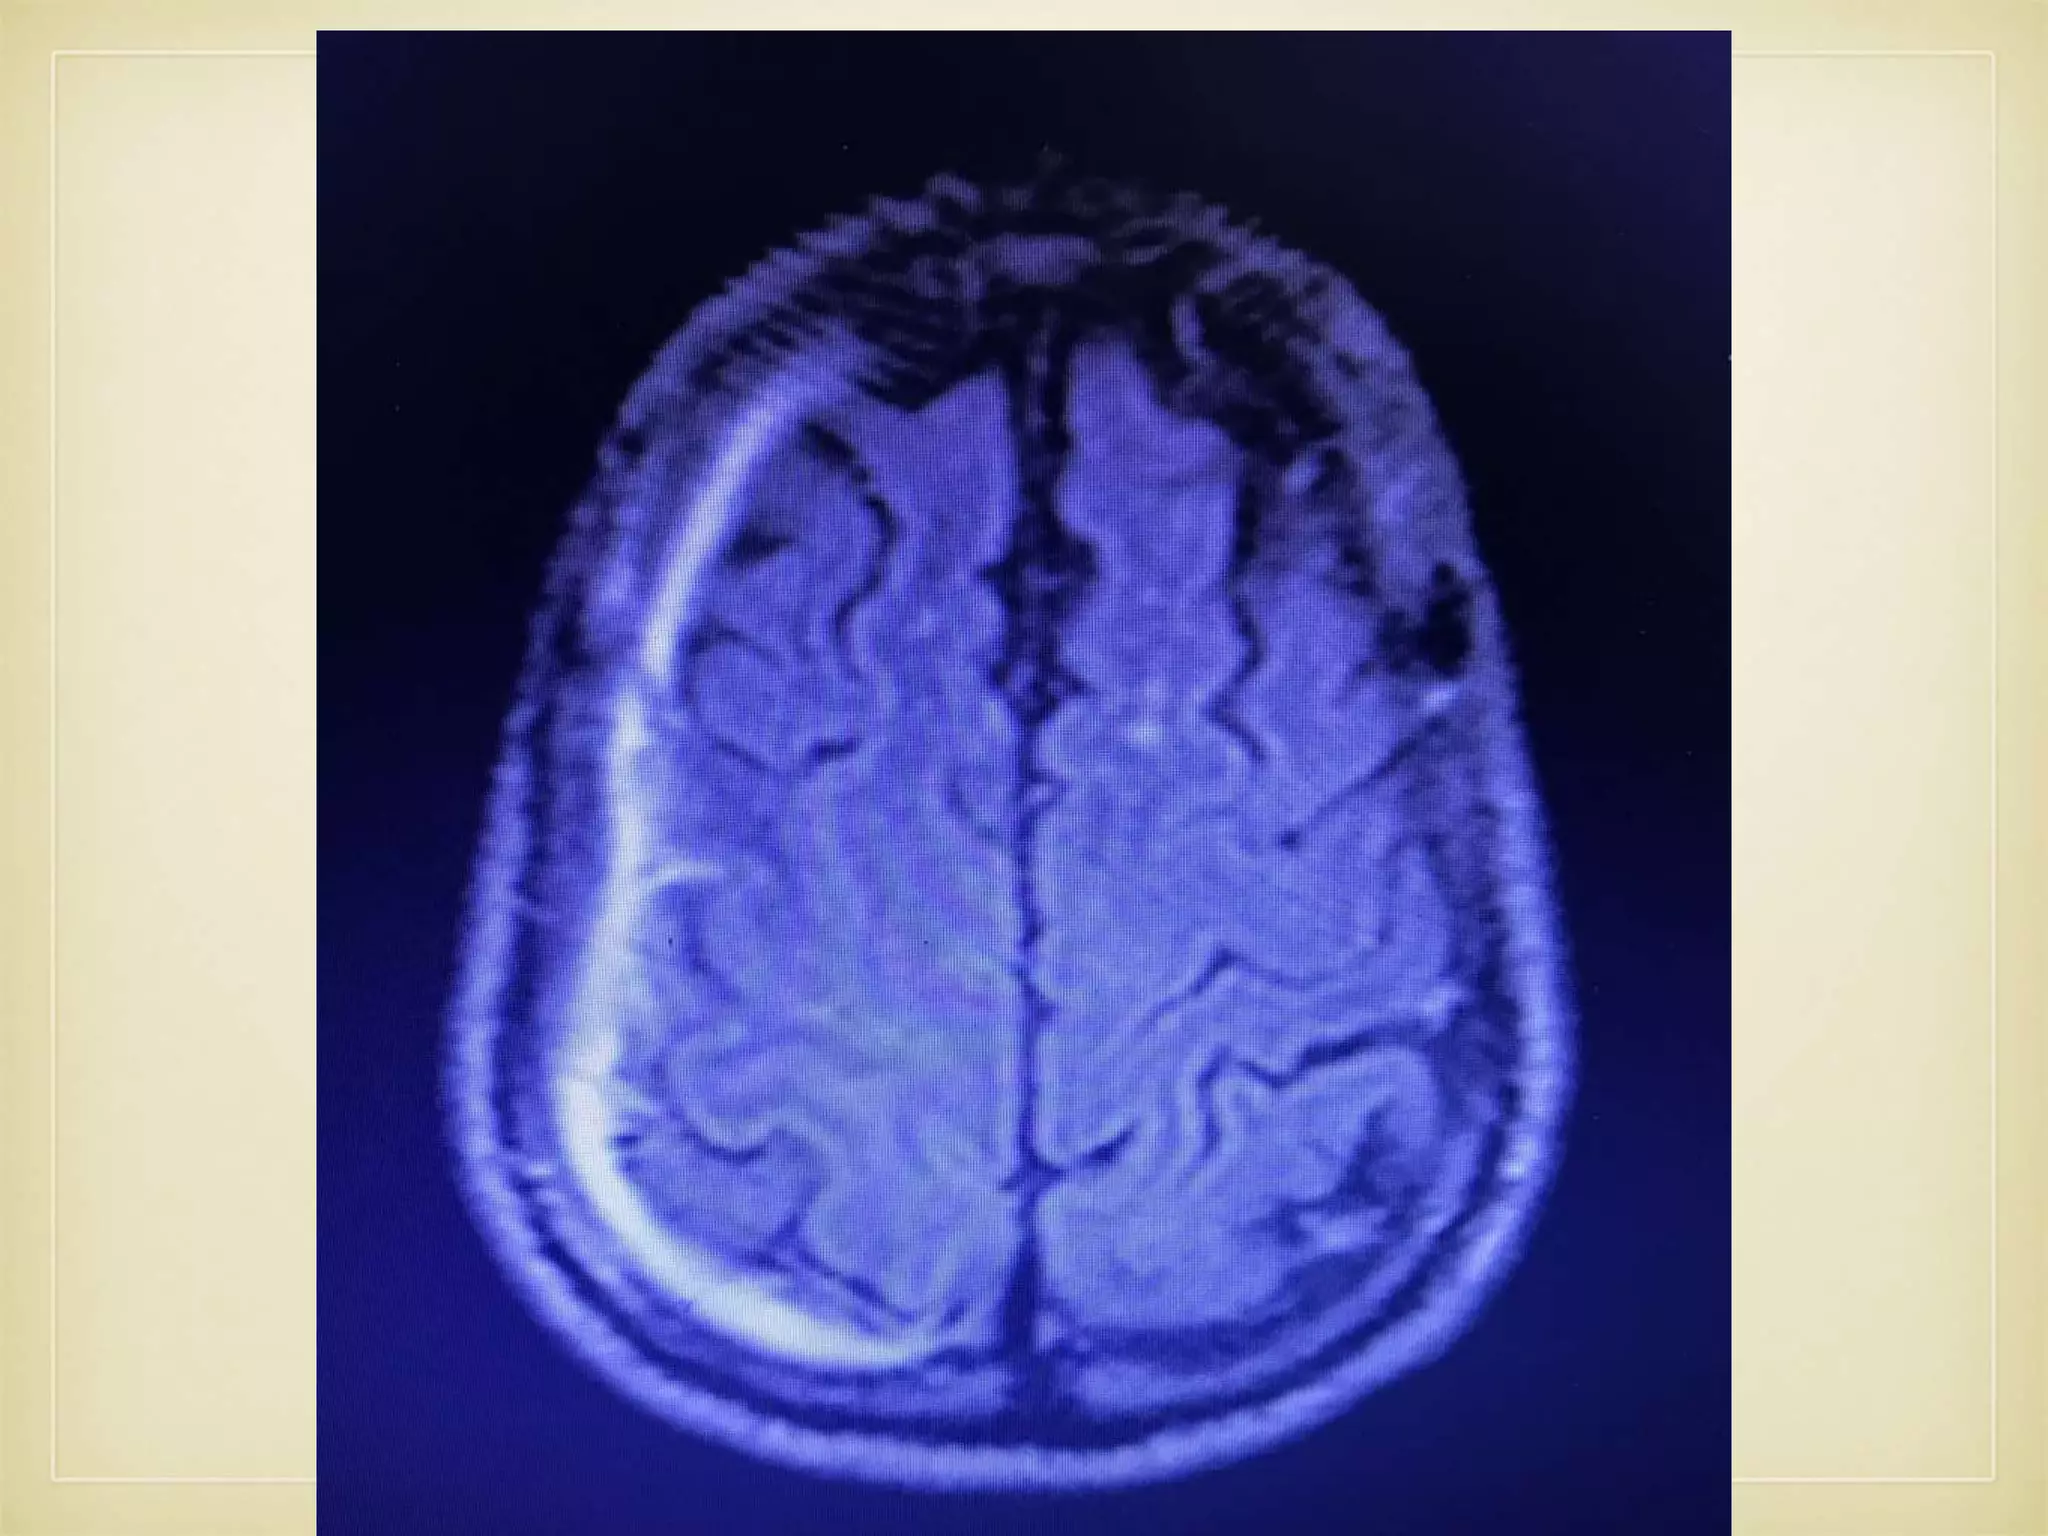

• Further evaluated with MRI brain and MRA

IMAGING

• CT Brain- SDH Rt. Fronto-temporo-parietal region • MRI C.Spine - C4-5, C5-6 disc bulging with compression of C5/6 roots on R>L with facet joint hypertrophy

• Again Readmittedon 22.12.2107 with ℅ Paroxysmal Dysarthria - 2 times lasting for 10- 15 times and recovers fully. • No other associated symptoms • Further evaluated with MRI brain and MRA